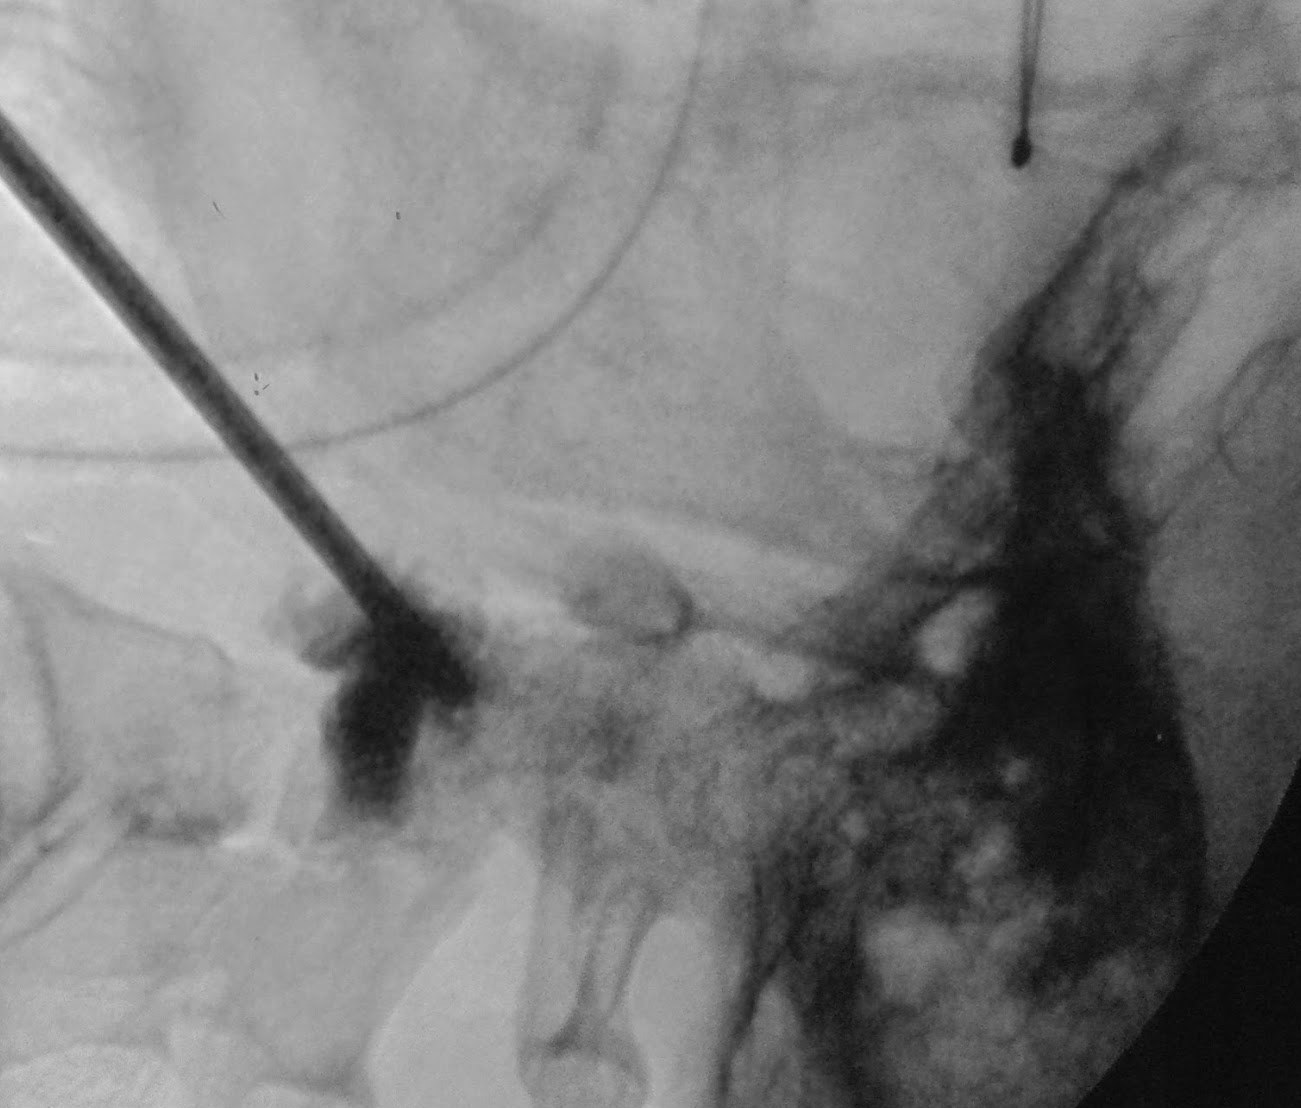

圖一: 穿刺針刺入頸椎骨折的脊椎骨

圖二: 灌入骨水泥(黑色顯影處)